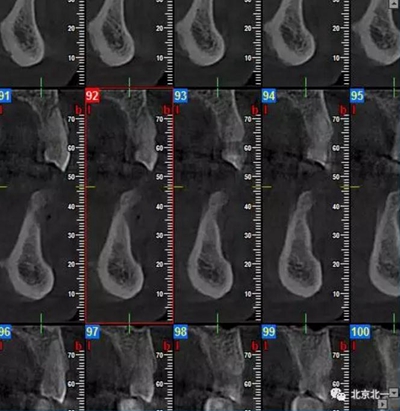

CBCT顯示如下圖